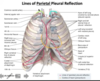

-

apex lung = cervical portion parietal pleura

- extend a couple centimeters above the clavicle

- bilaterally descends toward sternal line obliquely

- right parietal pleura follows sterunum and moves l_aterally at 6th rib_

- left parietal pleura follows sternum and moves laterally at 4th costal cartilage to accomidate heart and pericardium

- bilaterally reach mid clavicular line at 8th costal cartilage

- bilaterally reach mid axillary line at 10th rib

- inferior margin of parietal pleura by scapular line is at 11th rib

- paravertebral line, the pleura is inferior to neck of the 12th rib

What is the general rule fot he difference in location betweenthe lung margins and pleural lines?

- lungs are ~2 ribs superior at MCL, MAL, PVL

- MCL at 8 : lungs at 6

- MAL at 10 : lungs at 8

- PVL at 12 : lungs at 10